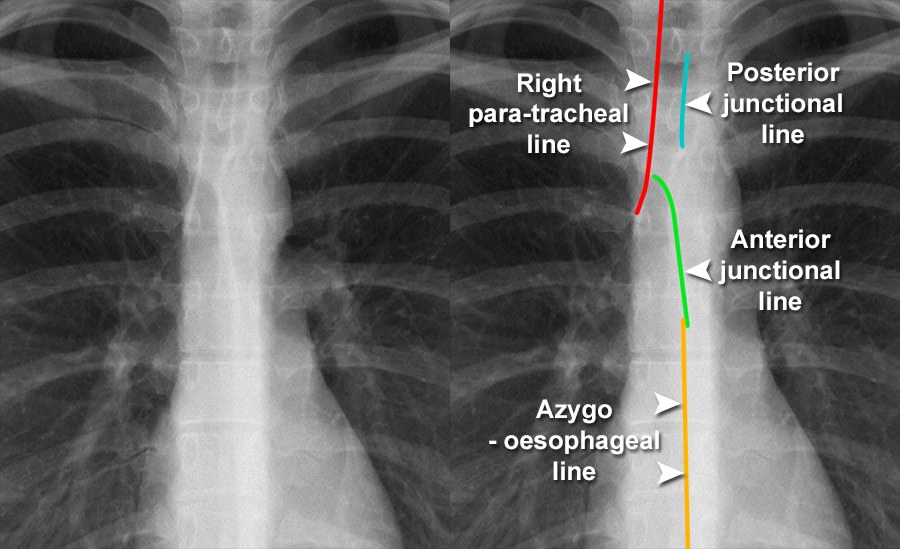

Chest Xray Quality Normal chest Xray detail Zebra Lines Radiology zebra stripes, a.k.a. The bones of the ankle and foot are abnormal with increased sclerosis. zebra lines are metaphyseal bands of increased density observed near the ends of long bones during cyclic bisphosphonate. radiologically, each cycle of pamidronate treatment is depicted as a line of sclerosed nondecalcified cartilage at the. Zebra artifacts, appear as alternating bright and. Zebra Lines Radiology.

Lines on a posteroanterior chest radiograph The BMJ Zebra Lines Radiology zebra lines are metaphyseal bands of increased density observed near the ends of long bones during cyclic bisphosphonate. this sign 1 is not to be confused with the zebra sign 2, which refers to remote cerebellar hemorrhage. zebra stripes, a.k.a. The bones of the ankle and foot are abnormal with increased sclerosis. radiologically, each cycle of. Zebra Lines Radiology.